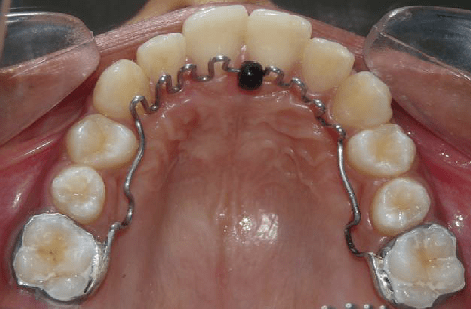

2. Palatal Expanders

Photo by Graziano Montaruli – ResearchGate

Palatal expanders can widen the upper jaw and create more space for permanent teeth, potentially treating dental issues like overbites, overcrowded teeth, and impacted teeth.

These appliances gradually widen the upper jaw by applying gentle pressure to the palatal bones, which are still malleable in children.